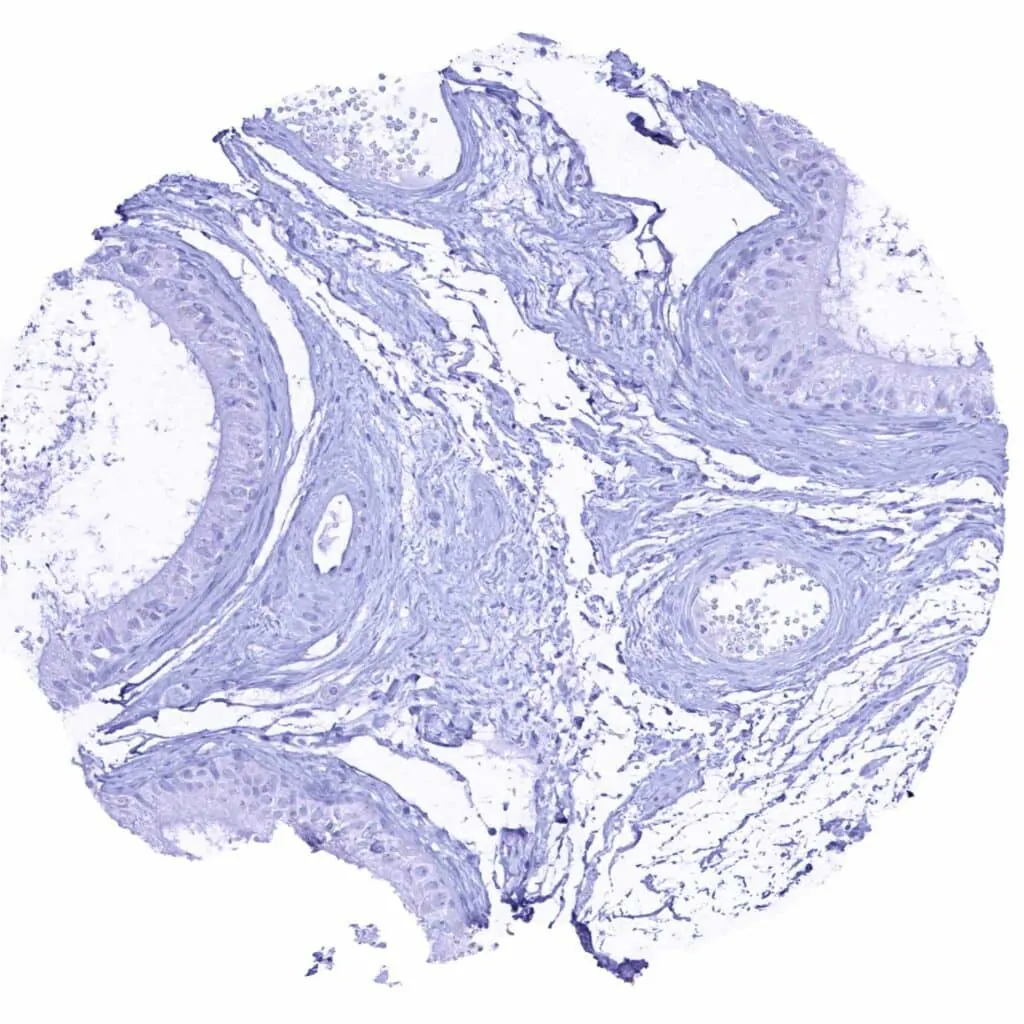

Skin, hairfollicel and sebaceous glands

Skin